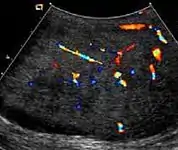

Fig. 3. Seminoma. (a) Seminoma usually presents as a homogeneous hypoechoic nodule confined within the tunica albuginea. (b) Sonography shows a large heterogeneous mass occupying nearly the whole testis but still confined within the tunica albuginea, it is rare for seminoma to invade to peritesticular structures.

Approximately 95% of malignant testicular tumors are germ cell tumors, of which seminoma is the most common. It accounts for 35%–50% of all germ cell tumors. Seminomas occur in a slightly older age group when compared with other nonseminomatous tumor, with a peak incidence in the fourth and fifth decades. They are less aggressive than other testicular tumors and usually confined within the tunica albuginea at presentation. Seminomas are associated with the best prognosis of the germ cell tumors because of their high sensitivity to radiation and chemotherapy.

Seminoma is the most common tumor type in cryptorchid testes. The risk of developing a seminoma is increased in patients with cryptorchidism, even after orchiopexy. There is an increased incidence of malignancy developing in the contralateral testis too, hence sonography is sometimes used to screen for an occult tumor in the remaining testis. On US images, seminomas are generally uniformly hypoechoic, larger tumors may be more heterogeneous [Fig. 3]. Seminomas are usually confined by the tunica albuginea and rarely extend to peritesticular structures. Lymphatic spread to retroperitoneal lymph nodes and hematogenous metastases to lung, brain, or both are evident in about 25% of patients at the time of presentation.